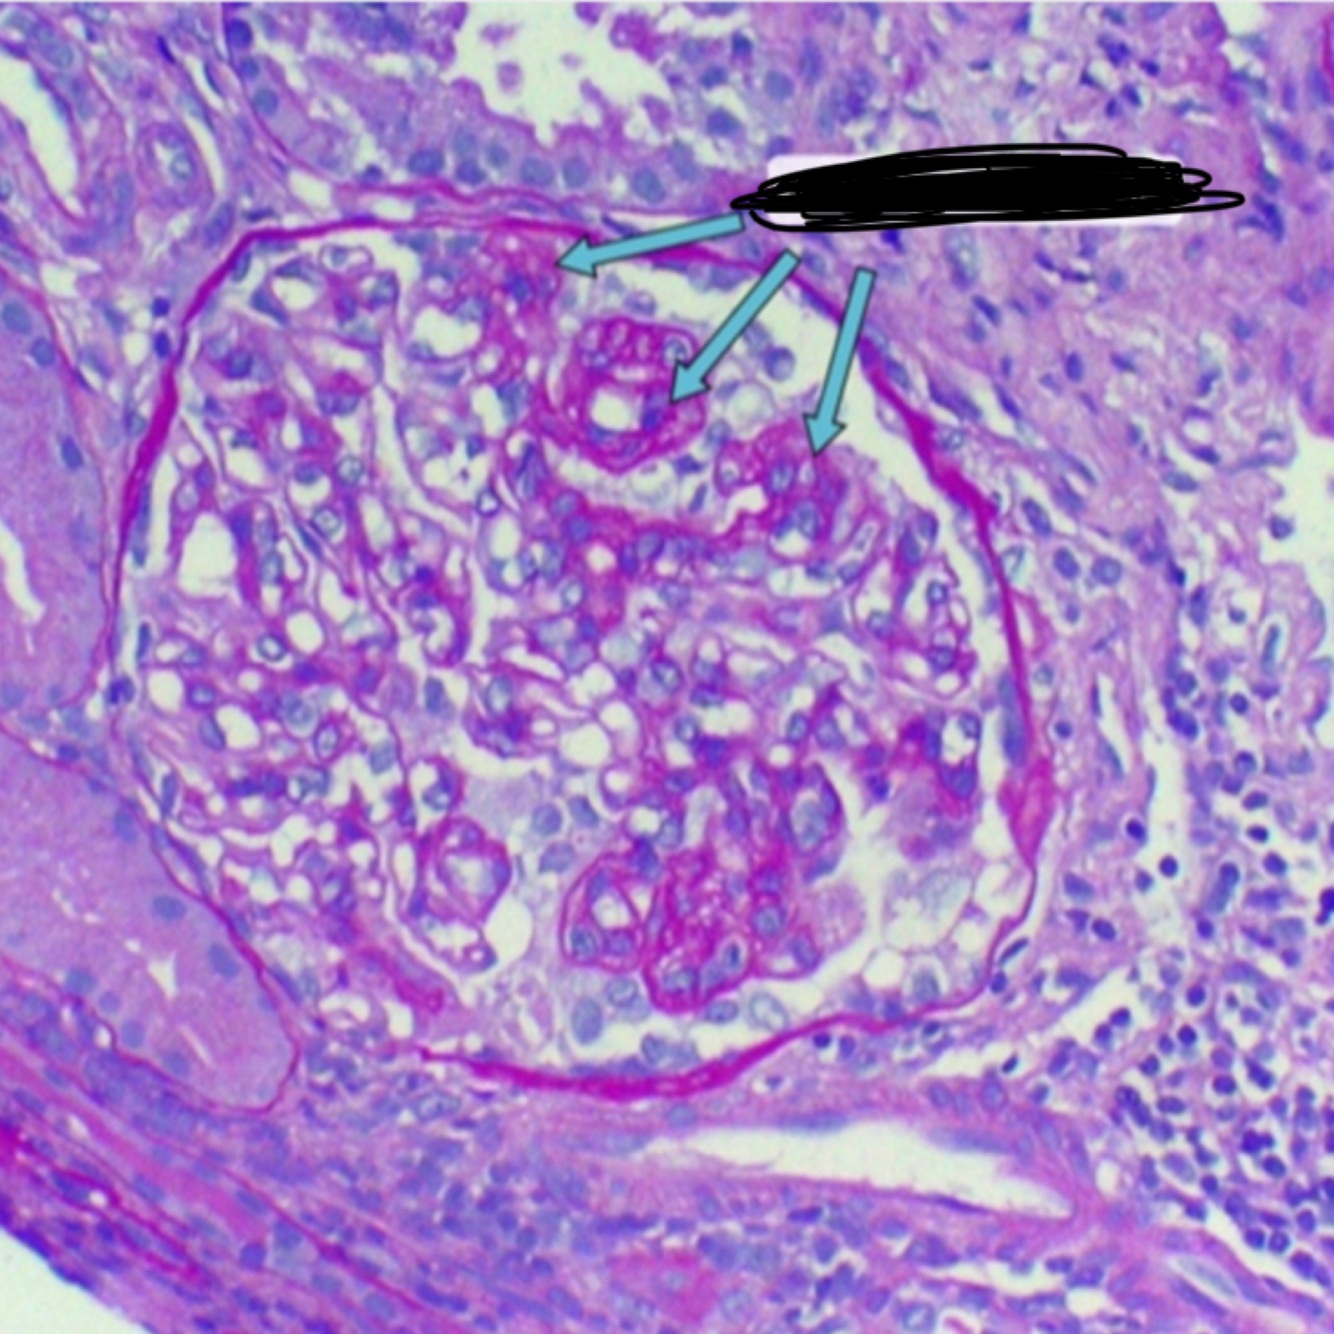

renal biopsy shows nodular sclerosis (also called Kimmelstiel-Wilson nodules), which is characteristic of advanced diabetic nephropathy

lupus nephritis, wire-loop” appearance,